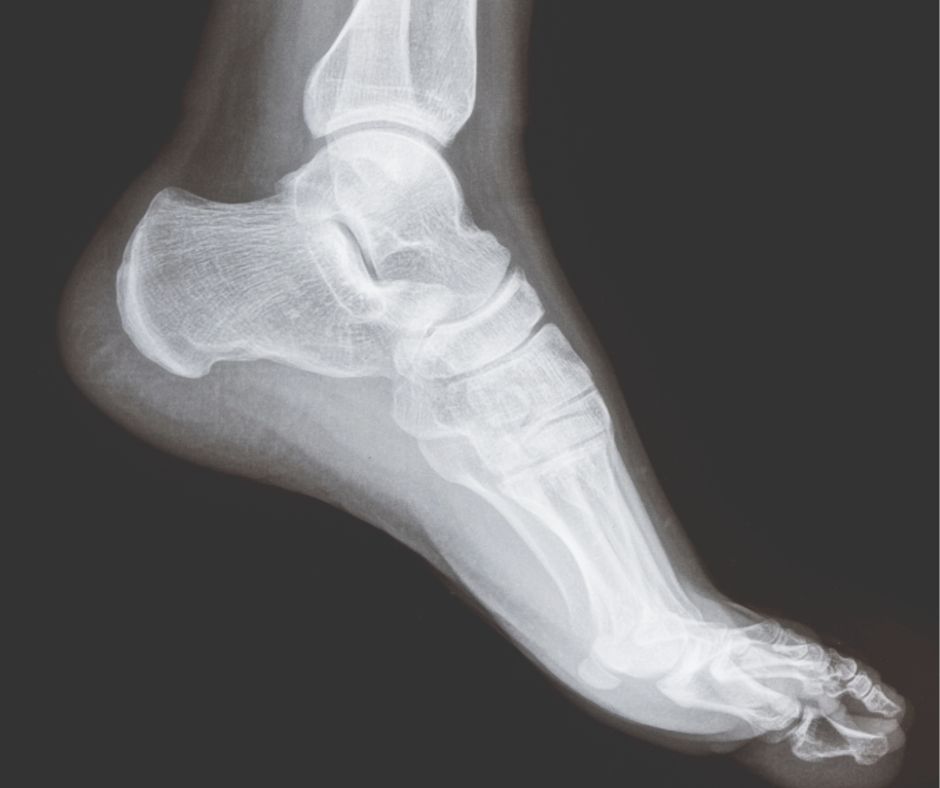

When to Refer for Imaging: X-ray in Foot and Ankle Pain

X-ray imaging remains a fundamental first-line investigation in the assessment of foot and ankle pain. While not all patients require imaging, understanding when to refer